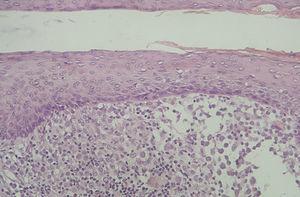

En la HCL el infiltrado se localiza normalmente en la dermis adventicial, y puede invadir la epidermis, produciendo clínicamente lesiones erosivas (figs. 13 y 14). En las formas nodulares puede invadir la hipodermis. En pacientes adultos se ha descrito la distribución del infiltrado alrededor de los anejos (figs. 15 y 16) 13. Aparecen otras células inflamatorias en número variable, sobre todo neutrófilos, eosinófilos, linfocitos y mastocitos y, en menor medida, células gigantes multinucleadas. De forma clásica se han descrito tres subtipos principales: proliferativo, granulomatoso y xantomatoso, que se intentan correlacionar con las diferentes formas clínicas. Histológicamente no existen diferencias entre la HCL y la reticulohistiocitosis congénita autoinvolutiva 7.

Fig. 13.--Infiltrado en placa subepidérmico conformado por células de Langerhans. (Hematoxilina-eosina,x10.)

Fig. 14.--A mayor aumento, detalle del infiltrado en dermis reticular. (Hematoxilina-eosina, x20.)